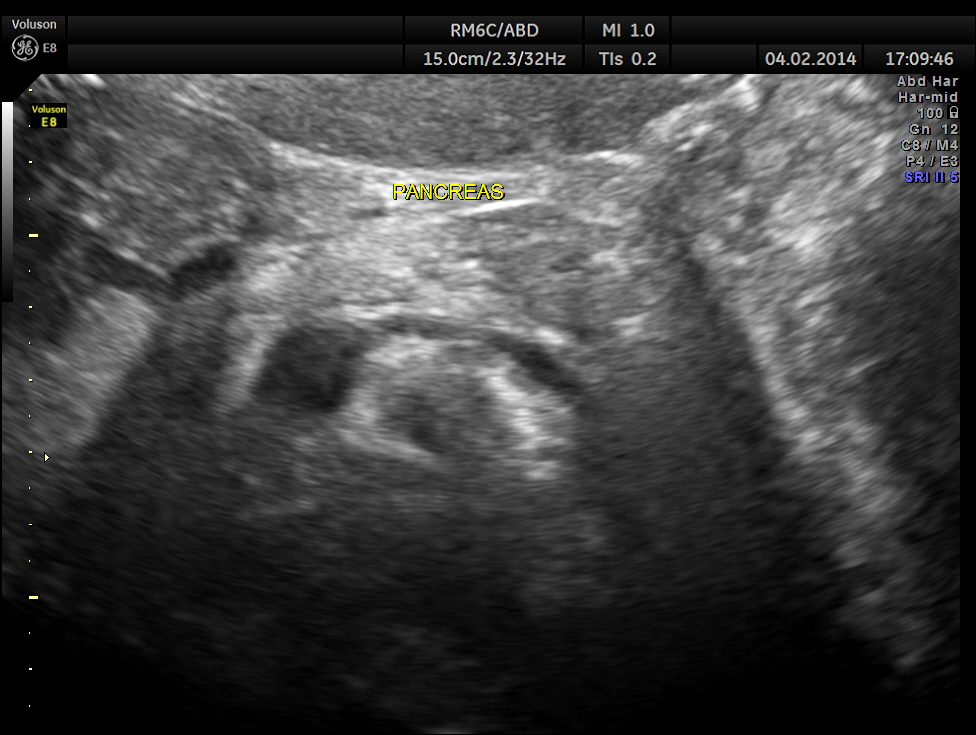

The pancreas appeared to be normal.